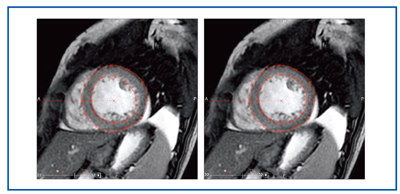

図1 心臓MRIプロトコル a:シネMRI、b:Black blood MRI c:パフュージョンMRI、d:遅延造影MRI

図1 心臓MRIプロトコル

a:シネMRI、b:Black blood MRI

c:パフュージョンMRI、d:遅延造影MRI

当院では、Signa HDxt 1.5T(GE社製)を心臓MRIに用いている。心臓MRIの年間検査数は約180件、主な依頼理由は心筋症をはじめとする心不全である。心臓MRIルーチン撮像プロトコルは、black blood MRI、シネMRI、パフュージョンMRI(安静時)、遅延造影MRIである(図1)。負荷時のパフュージョンMRIは、現状では施行していない。